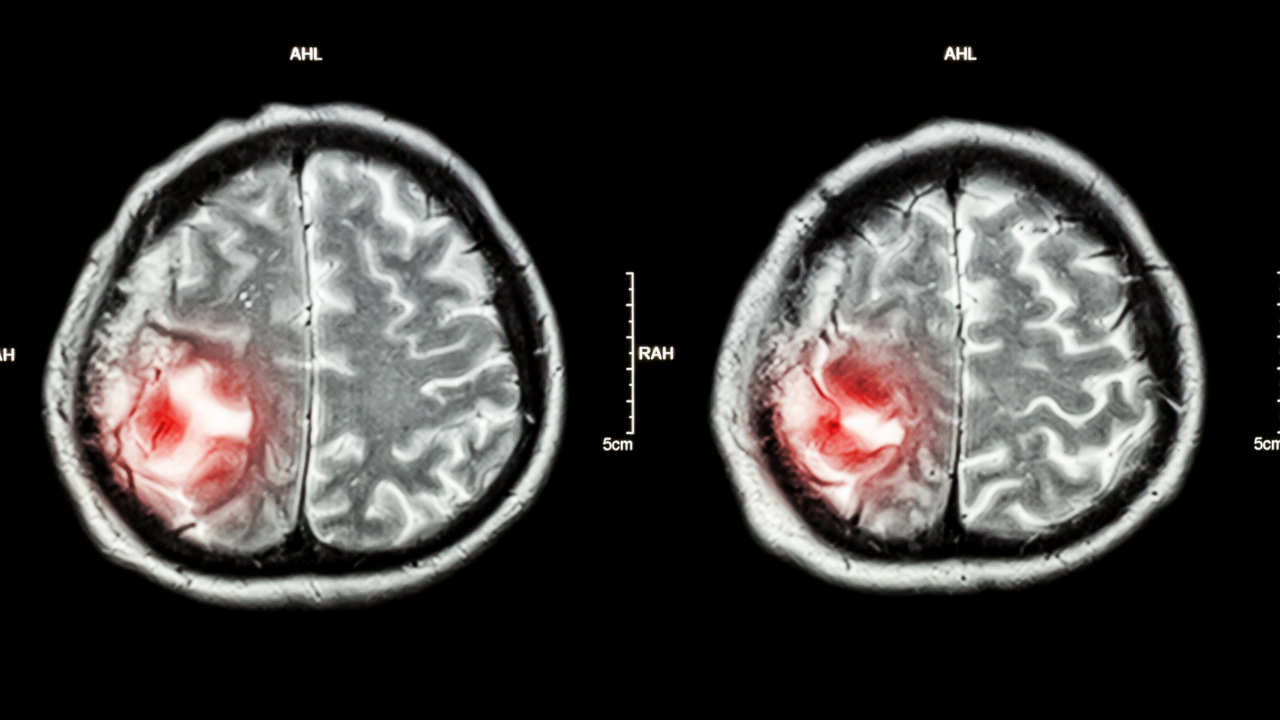

MR (Manyetik Rezonans): Beyin dokusunu en net gösteren yöntemdir. Genellikle ilaçlı (kontrastlı) MR çekilerek tümörün damarlanma yapısı incelenir.